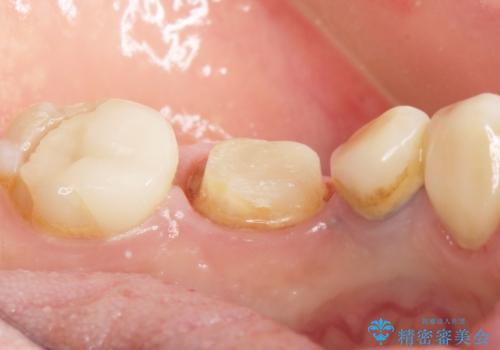

- 奥歯の被せ物をセラミックにしたいとご希望され、来院された患者様です。

左下の奥歯(左下6)の劣化した白い被せ物と金属の土台を除去し、セラミッククラウンによる補綴治療を行いました。